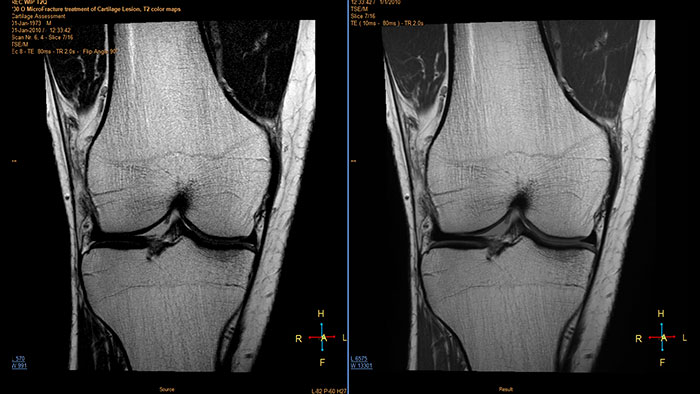

Optimizing image contrasts for multi-echo MR data

MR Echo Accumulation enables the calculation of new images based on the selected sum of echo times.

Benefits